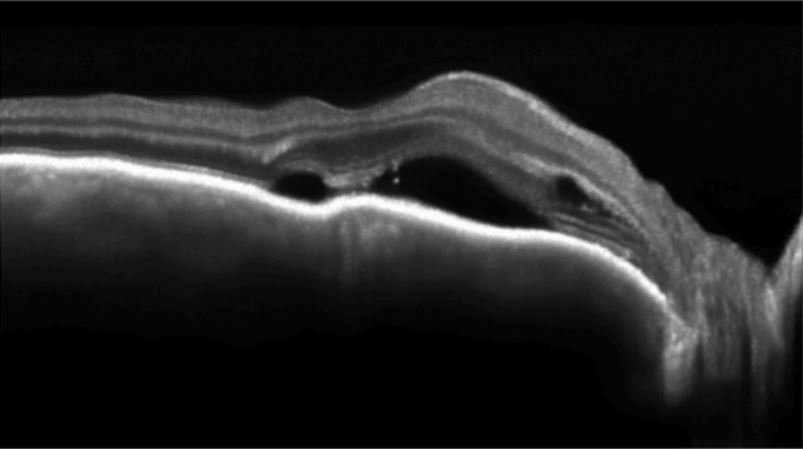

High definition vascular microcirculation imaging Function integration

- Visualization of 3D fundus imaging

- Rich details between layers

- High-resolution fundus imaging